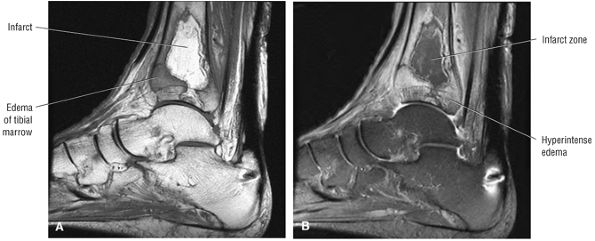

Stage I: Subchondral trabecular compression. Radiograph results are negative, bone scans are posi-tive, and marrow edema is seen on MR imaging (Fig. 5.95).

Stage IIA: A subchondral cyst (Fig. 5.96)

Stage IIB: Incomplete separation of the fragment (Fig. 5.97)

Stage III: Fluid around a nondetached, nondisplaced fragment (Figs. 5.98 and 5.99)

Stage IV: A displaced fragment (Fig. 5.100)